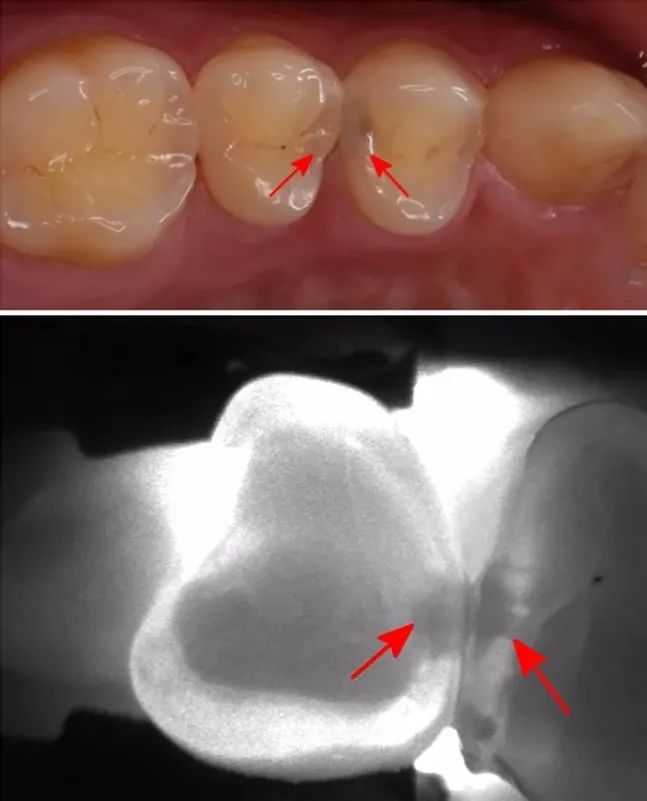

因?yàn),有些齲齒用肉眼并不能直接觀察到,它們不存在于表面,而是隱藏在深處。初期一般沒有明顯癥狀,常常難以被注意到;等到為人所察覺時(shí),往往就已經(jīng)爛得有些深了。若得不到及時(shí)治療,最終會形成牙髓炎或根尖周病,進(jìn)而影響生活質(zhì)量。對付這種隱蔽的口腔健康威脅,最有效的辦法就是定期進(jìn)行口腔檢查。

齲齒的發(fā)展是一個(gè)由淺至深的過程。起初牙齒會有點(diǎn)變色,出現(xiàn)一些小黑點(diǎn)和小黑線。此時(shí)已經(jīng)發(fā)生了淺齲,需要做藥物治療或充填治療。